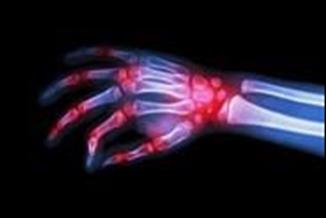

האם פיברומיאלגיה תוגדר כמחלה אוטואימונית?

במשך שנים רבות האמינו חוקרים שפיברומיאלגיה היא מחלה שמקורה במוח. האם ייתכן שזו בכלל מחלה אוטואימונית, שמקורה במערכת החיסונית? מחקר חדש טוען שנמצאה תשובה לתעלומה

למרות הדעה הרווחת שמקור המחלה הוא במוח, מחקר בריטי חדש[3] שפורסם בכתב העת Journal of Clinical Investigation, טוען כי ממצאיו הראו שרבים מהתסמינים של פיברומיאלגיה נגרמים כתוצאה מנוגדנים הגורמים לפעילות מוגברת של עצבים של חישת כאב.